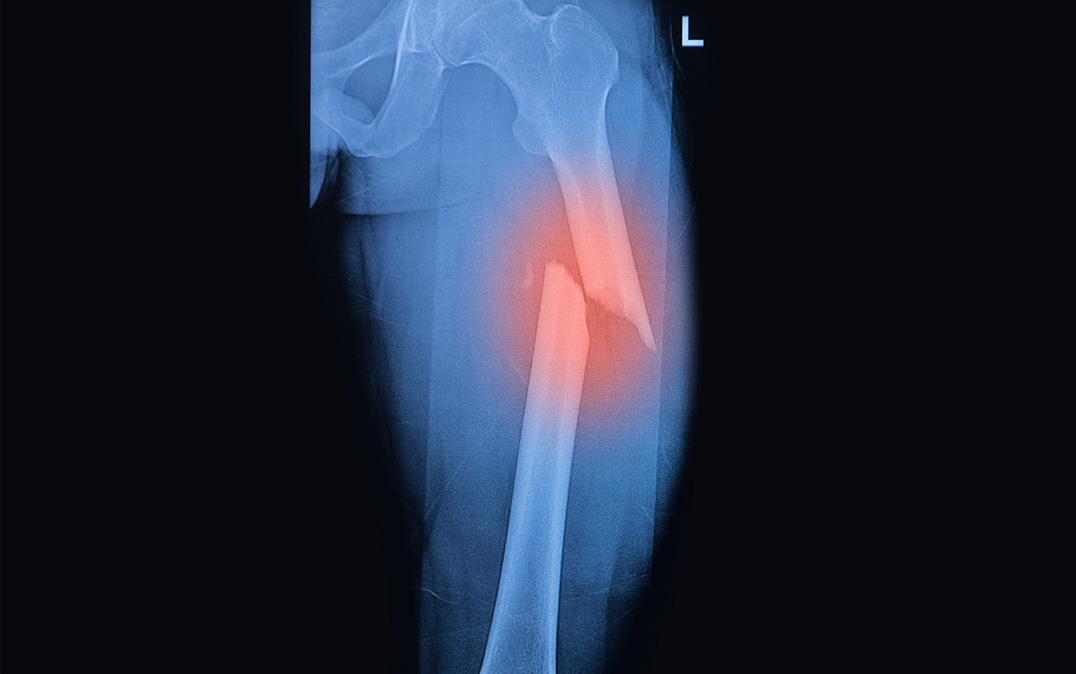

研究イメージ画像 (Image by Praisaeng/Shutterstock)

このマウスからCD73陽性MSCsとCD73陰性MSCsを単離し、性質を比較したところ、CD73陽性MSCsは、生体外において高い増殖能と骨・軟骨細胞への分化能を持つことが分かりました。また、マウス大腿部に骨折を作製し、骨修復におけるCD73陽性MSCsの動態解析より、CD73陽性MSCsは骨折部位に遊走し、骨芽細胞や軟骨細胞に分化し、積極的に組織修復に関わっていることが判明しました。一方、CD73陽性血管内皮細胞は、骨修復中期に骨折部位に観察され、周囲には造血幹前駆細胞が集積し、ニッチの再構築に働いていました。以上のことから、CD73発現細胞はニッチの再構築に重要な役割を示すことが明らかとなりました。